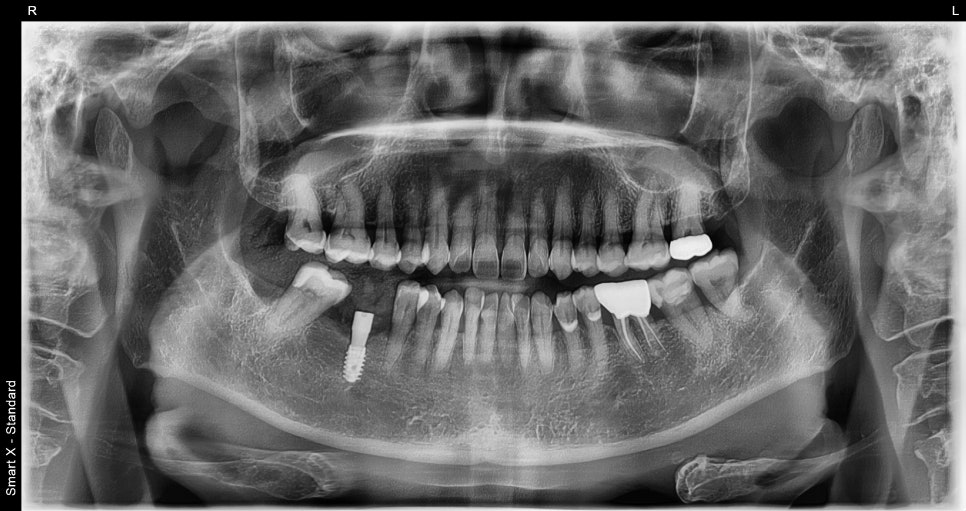

수술 직 후 엑스레이 사진

✔️ 저작 기능 완전 회복

✔️ 반대편 어금니 부담 감소

✔️ 주변 치아 쓰러짐 방지

✔️ 교합 균형 정상화